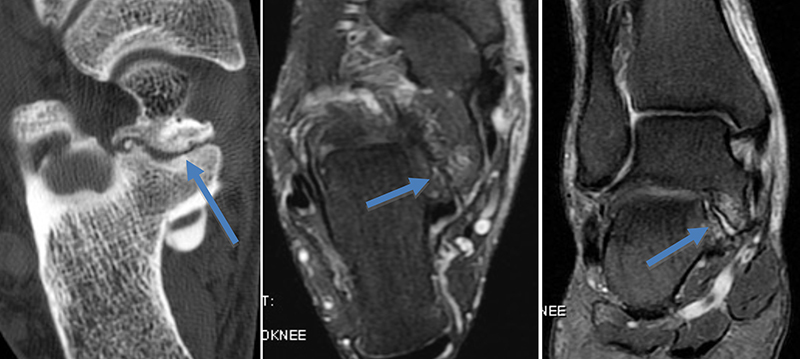

Dégénérescence myxoïde du LCA (kyste infiltrant du LCA)